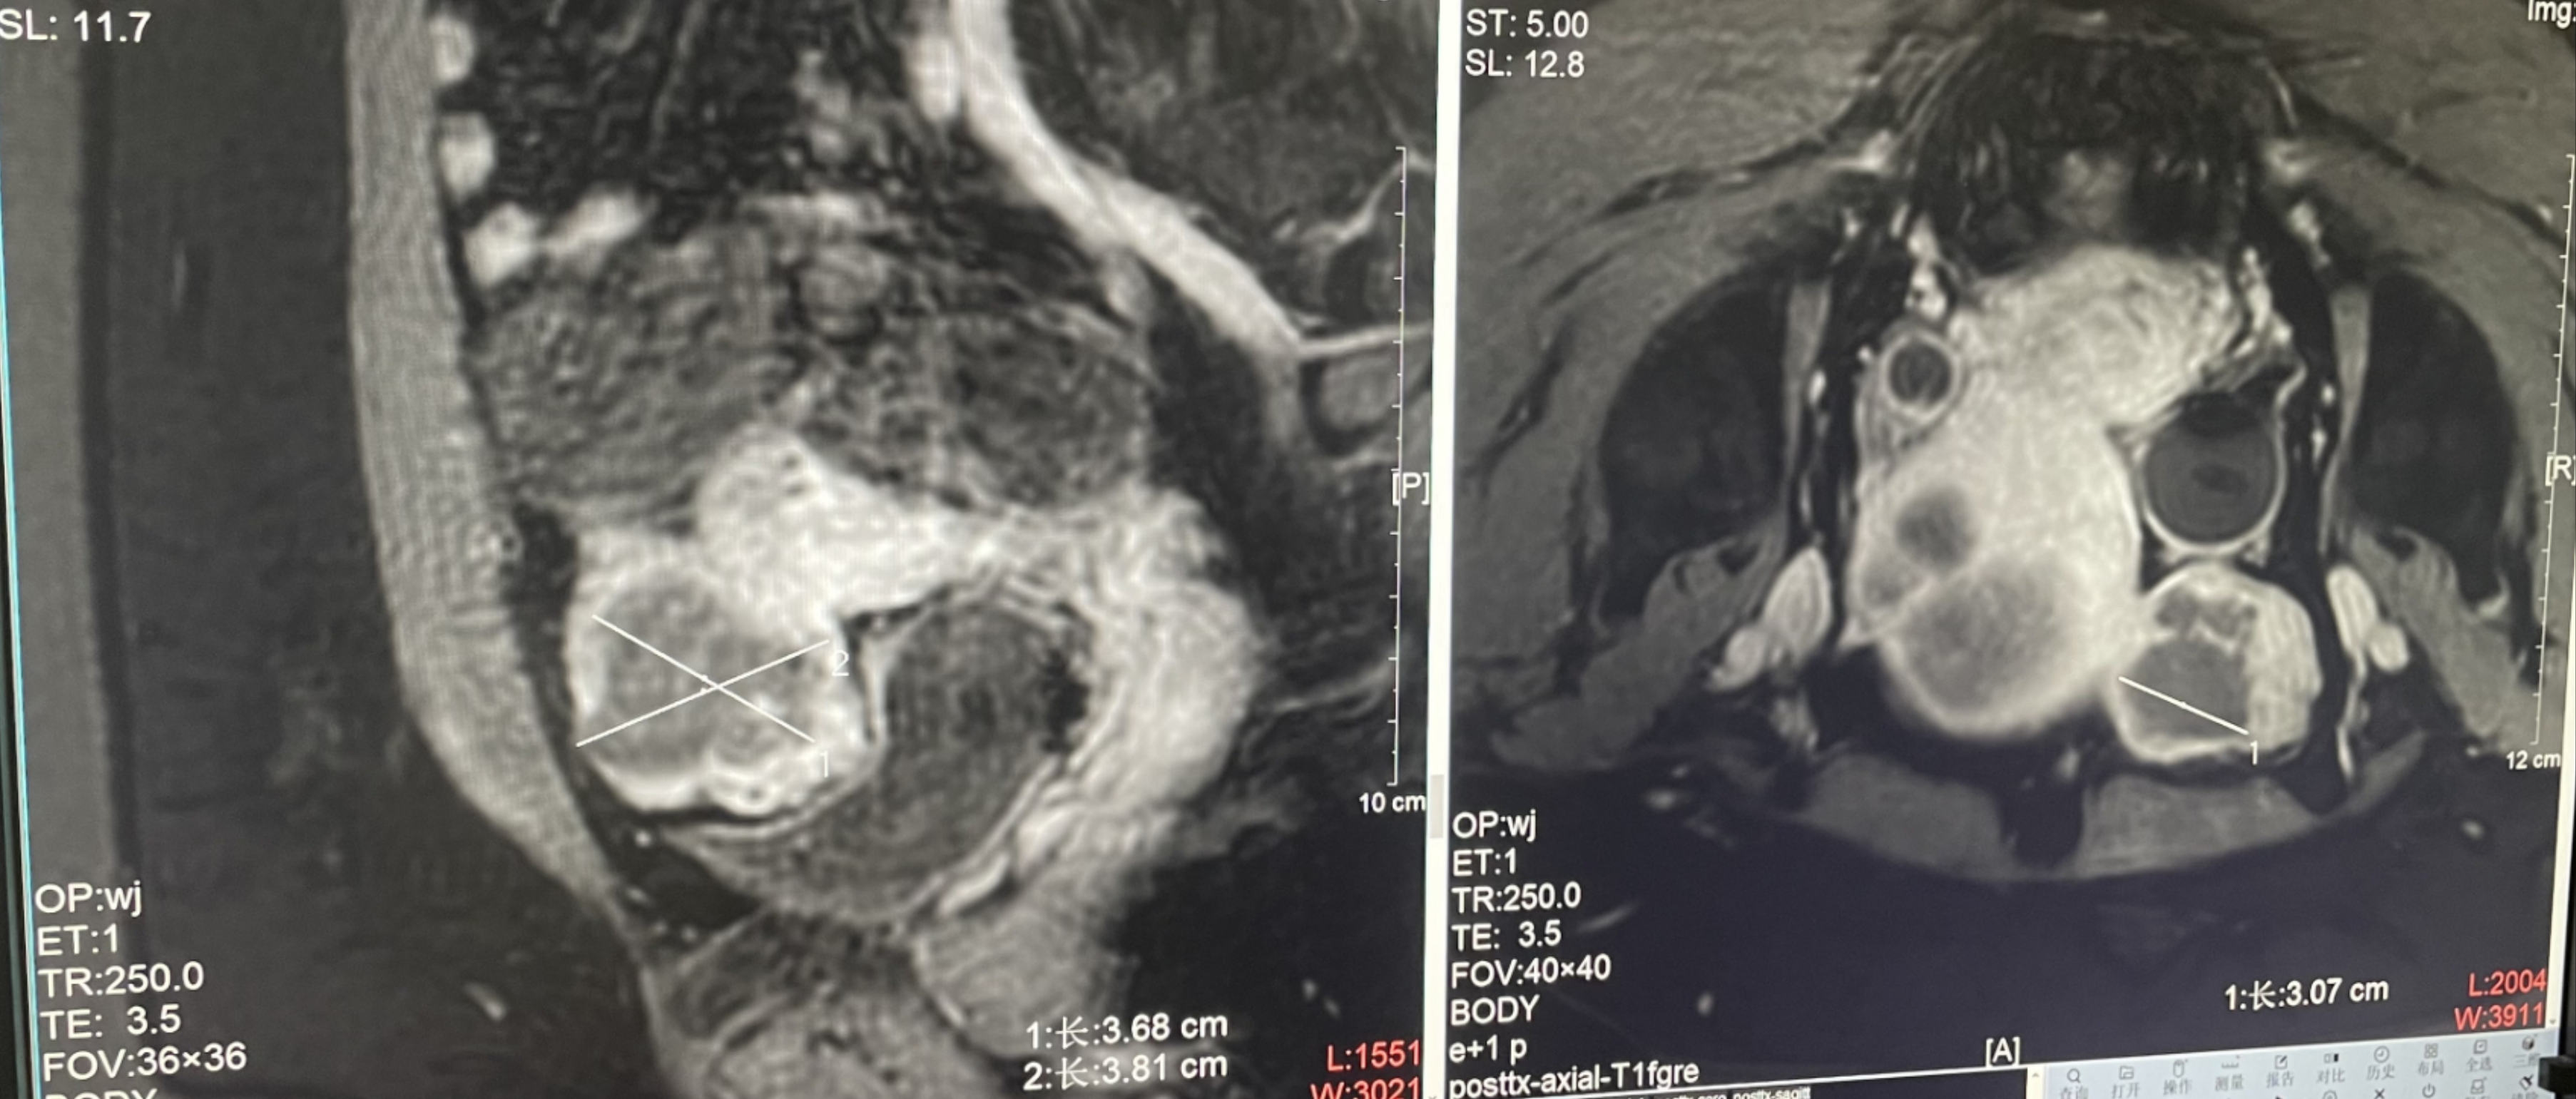

Postoperative evaluation: Postoperative enhanced imaging showed a good overlap between the ablation area (right) and the tumor area (left), the non-perfusion area was continuous and consistent.

Conclusion:It has a excellent ablation effect on this tumor, and the temperature rise curve during treatment is in line with expectations. The 240CEM area of each treated target is large, full and continuous.The ablation effect was very good,the NPV volume ratio was about 87.88%.